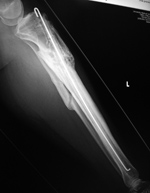

| A long stem bipolar hip prosthesis has cerclage wires in the diaphysis of the femur. From Hunter, 1994 |